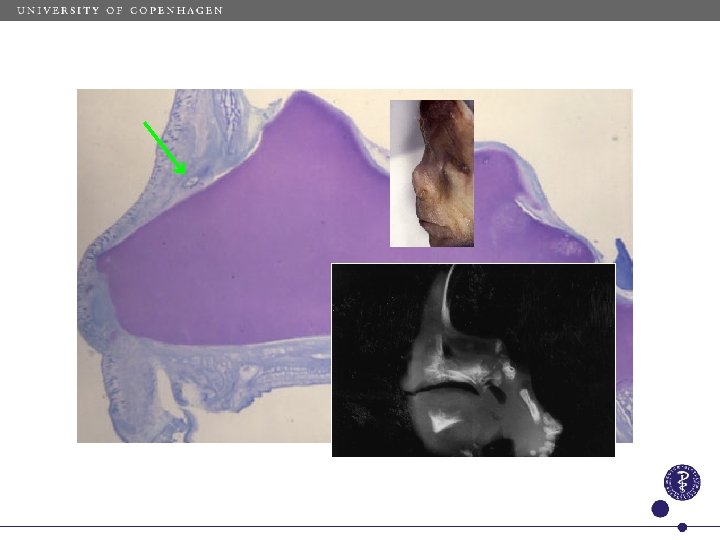

Normal development Os nasale